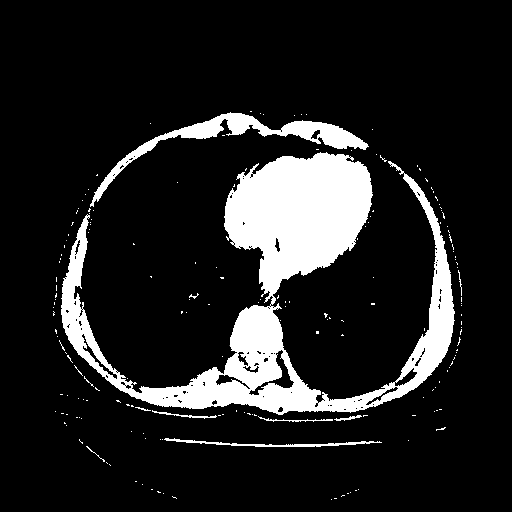

Image Grid

4Γ—3 grid: Rows show different image types (Original NATIVE, Reconstructed NATIVE, Original VENOUS, Generated VENOUS), Columns show windowing techniques (No Window, Lung Window, Mediastinum Window)

Original VENOUS CT scan

Full window (WL 1023.5, WW 4095 β†’ Low βˆ’1024, High +3071)

Actual HU range: [-1024.0, 3071.0]